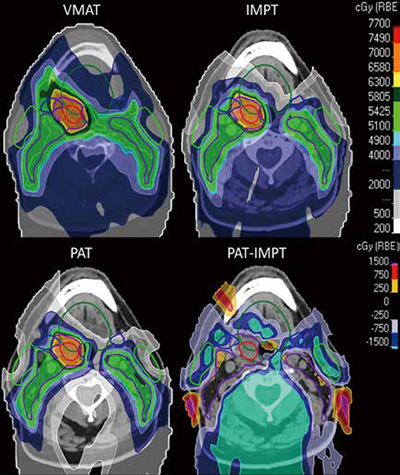

口咽鳞状细胞癌 质子放疗对比IMRT骨放射性坏死率更高

美国纪念斯隆-凯特琳癌症中心Yang等报告,在口咽鳞状细胞癌(OPSCC)患者中,与调强放疗(IMRT)相比,质子放疗与更高的骨放射性坏死(ORN)发生率相关,尤其在根治性治疗中,但两种疗法的高级别ORN仍然都较罕见。该回顾性发现应被视为探索性结果,强调了未来进行假设驱动研究时需优化剂量约束方案和治疗规划,从而降低OPSCC患者的ORN风险。(JAMA Otolaryngol Head Neck Surg. 2025年11月26日在线版)

ORN是头颈癌放疗可能引起的严重晚期并发症。虽然质子治疗在剂量拟合性方面具有优势,但其对ORN风险的影响仍不确定,尤其是在OPSCC患者中。